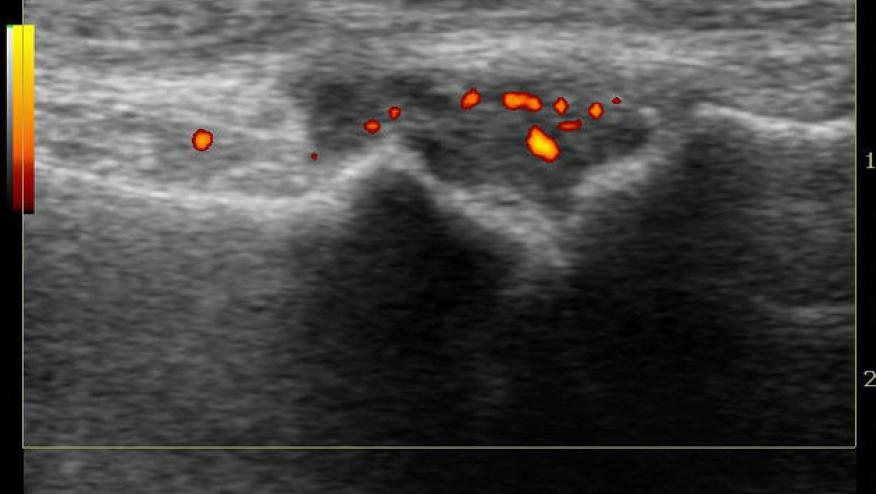

A total of 605 RA patients were studied serially with numerous clinical, outcome imaging (ultrasound) and laboratory outcomes. MDR required remission in 3 dimensions: A) Clinical: tender and swollen joint count (TJC/SJC) and CRP all ⩽1; B) ultrasound remission: total power doppler = 0 and C) T cell remission: positive normalized naïve T-cell frequency.

Ultrasound remission was seen in 211/364 (58%).